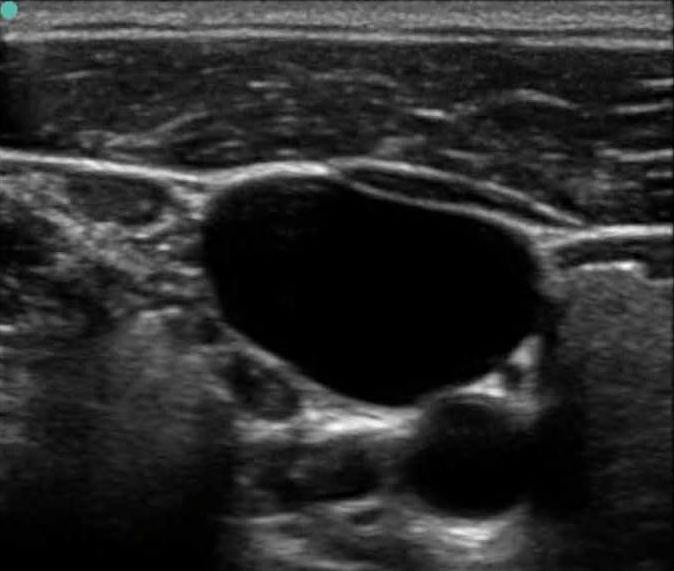

血管通路 2 图像

M-Turbo:IJV 短轴 2